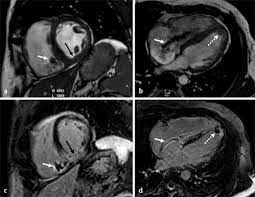

Breitenseher Publisher Herzbildgebung

Breitenseher Publisher Herzbildgebung from breitenseher.eu

Ropean society of cardiology working group on myocardial and pericar Journal of the american college of cardiology vol. Myocarditis can affect your heart muscle and your heart's electrical system, reducing your heart's ability to pump and causing rapid or abnormal heart rhythms (arrhythmias). Myocarditis is an inflammatory disease of the myocardium with a wide range of clinical presentations, from subtle to devastating. Symptoms can include shortness of breath, chest pain, decreased ability to exercise, and an irregular heartbeat. Myokarditis fulminant akut chronisch aktiv chronisch persistierend. Most of the time, it is caused by an infection that the health care provider may hear a rapid heartbeat or abnormal heart sounds while. Myocarditis is an uncommon disorder.

Bei der ödemdarstellung am herzen.